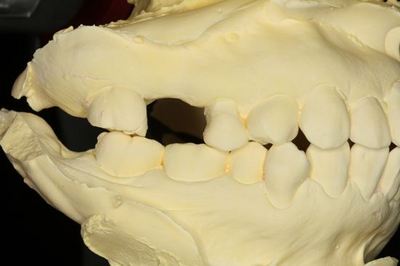

KaVo プロターevo7咬合器にマウントしました。

この部分にインプラントを植立します。

上下の歯の位置関係も確認します。

プラスチックでドリルガイドを作製します。(ライブピンクのレジンに意味はありません)